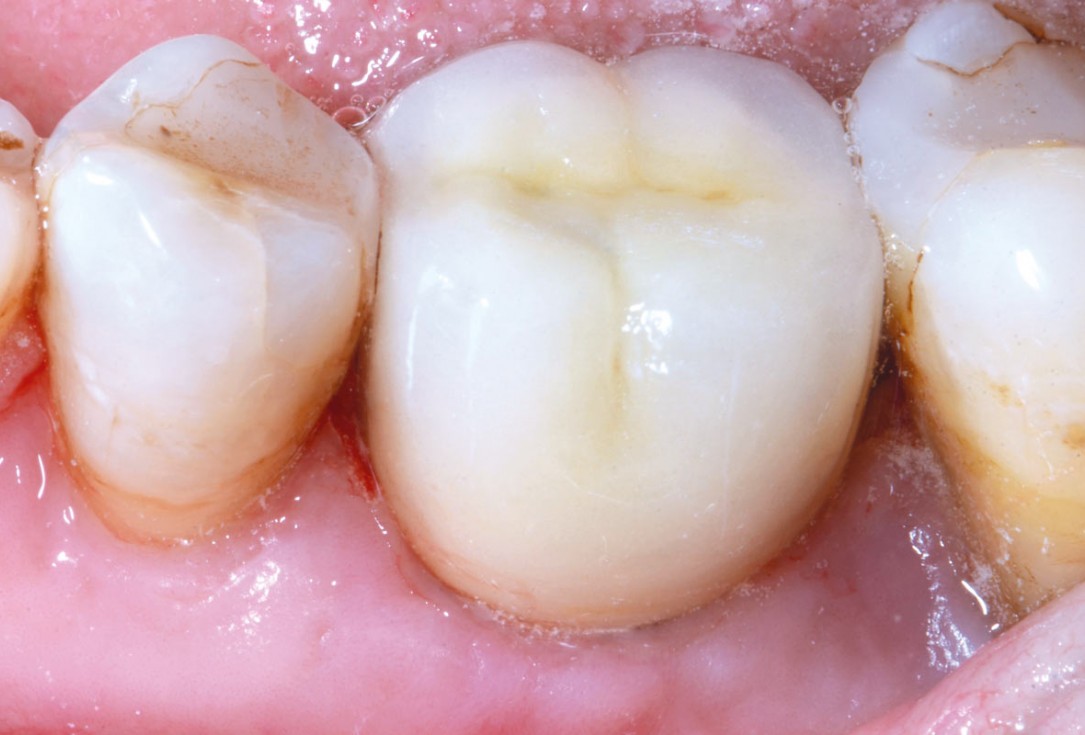

Immediate implant placement using cerabone® and collagen fleece - Dr. D. Jelušić

Pre-operative situation showing tooth 21 with deep periodontal pocket. Tooth presented with mobility grade III.